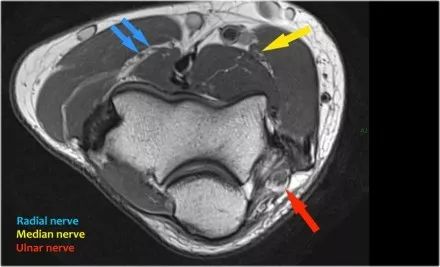

在研究韧带时,尤其是UCL,始终使用轴向图像。如果你看内侧上髁,你会发现后束是一个薄的结构(蓝色箭头)。注意在肘管内的尺神经。

后束形成肘管隧道的地板。支持带覆盖肘管。请注意,前束更厚(白色箭头)。您可以看到前韧带和后韧带之间的区别,即使它们形成一条韧带。走向远端,我们会看到它们合并在一起以附着于崇高的结节。